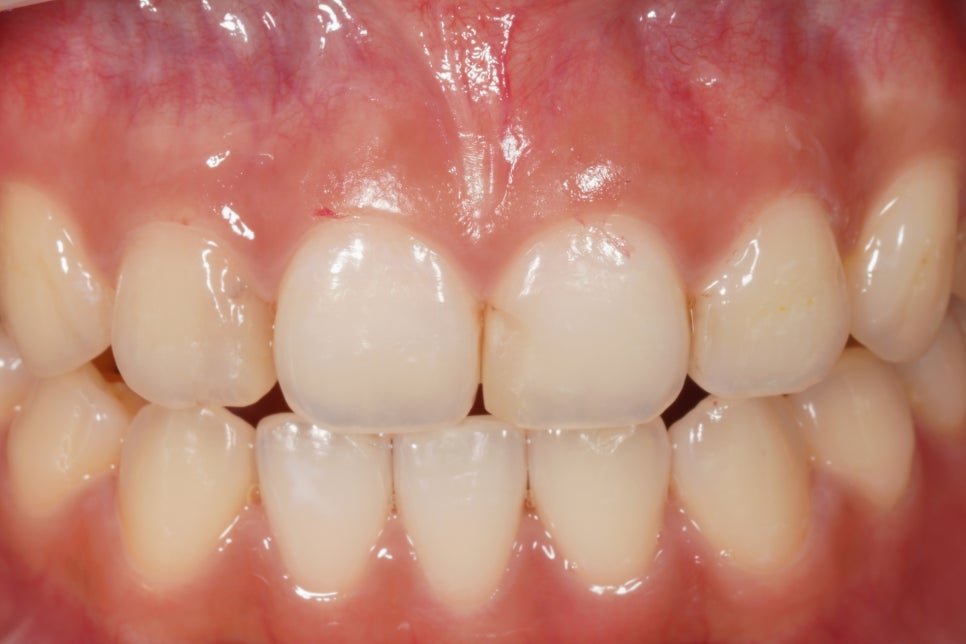

초진 사진

처음 오셨을 때 상태는 이랬는데요,

앞니 4개 사이에 5군데가

레진으로 치료되어 있었고,

변색이나 2차충치가 생겨있었습니다.